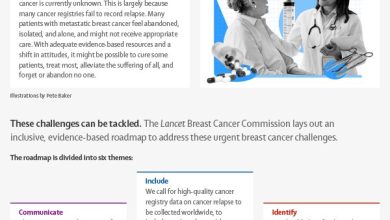

Many people with breast cancer ‘systematically left behind’ due to inaction on inequities and hidden suffering

Urgent breast cancer challenges can—and should—be tackled. Credit: The Lancet Breast cancer is now the world’s most common cancer; at…